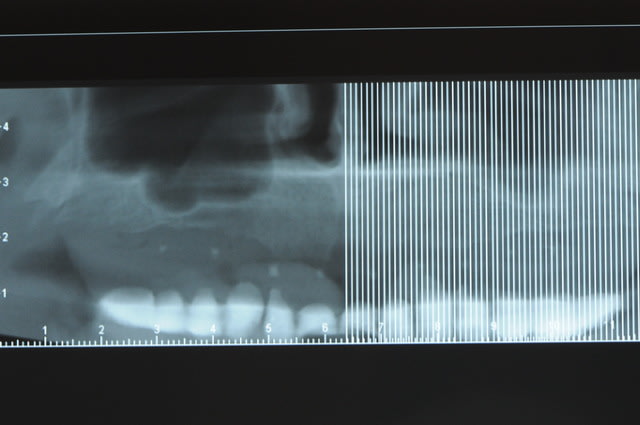

voili, voila...

avant de faire la tomosynthèse je comprenais pas pourquoi j'avais aussi peu de contraste.

le patient ne souhaite pas, ou ne peut pas se faire poser 6 implants en haut, donc...overdenture sur 4. (si possible)

Cas pour xpav e1rypn - Eugenol